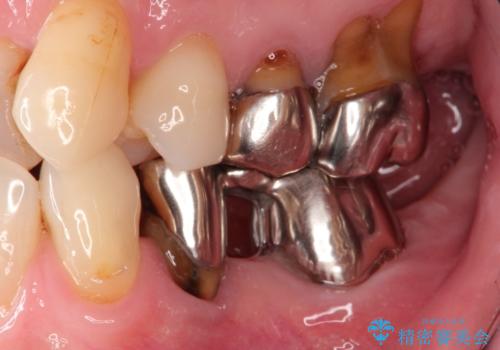

全顎修復 劣化したセラミックをやり直し 根管治療や歯周外科・インプラントも

- 古いセラミックを仮歯へ置き換えていく

→根管治療、歯周外科などをおこない土台となる歯のコンディションを整える

→同時にインプラントの埋入手術なども進行させていく

→奥歯から順次セラミックを完成させていく